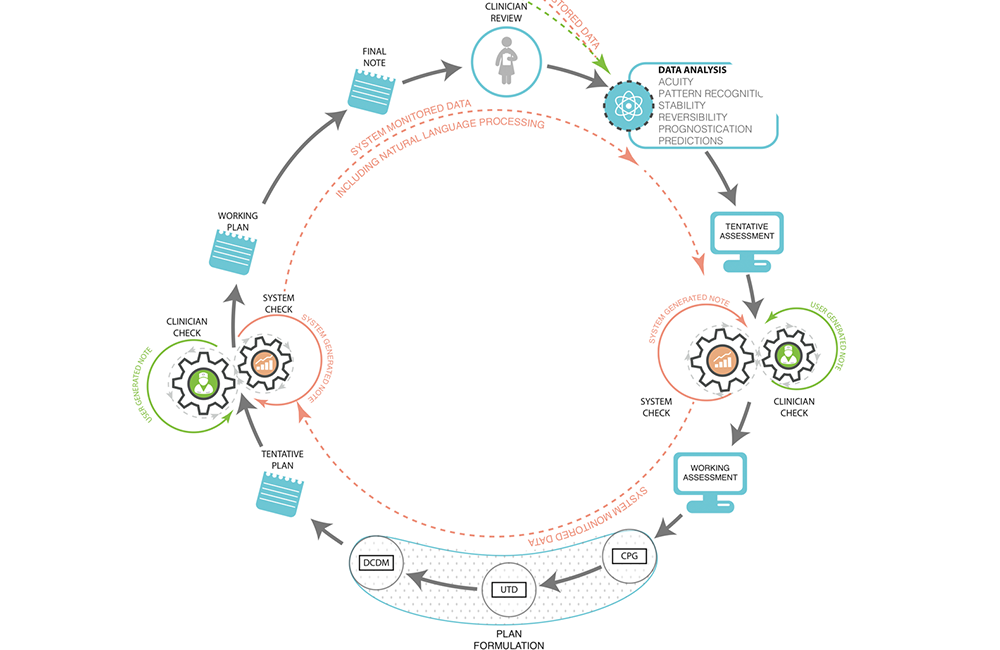

数据时代下的医疗数据与决策分析 | 2015 |《医疗数据信息学》

Celi, Leo A., Jeggery D. Marshall, Yuan Lai and David J. Stone. 2015. "Disrupting electronic health records systems: The next generation," Journal of Medical Informatics 3(4):e34.

数据整合用于城市健康 | 2020 | 《利用数据科学促进全球健康》Lai, Yuan and David J. Stone. 2020. "Integrated Data Intelligence for Urban Health," Book Chapter in Data Science and Global Health. Harvard-MIT Health Sciences and Technology. Springer.

大数据与医疗信息的结合应用 | 2016 | 《电子病历二次分析利用–医疗大数据分析方法导论》(中文版由人民卫生出版社于2019年出版)

Lai, Yuan, Edward Moseley, Francisco Salgueiro, and David J. Stone. 2016. "Integrating Non-clinical Data with EHRs" in Secondary Analysis of Electronic Health Records, MIT Critical Data Group, ed. Springer International Publishing AG.

数据时代的医疗数据决策分析 | 2016 | 《电子病历二次分析利用–医疗大数据分析方法导论》

Stone, David J., Justin Rousseau, and Yuan Lai. 2016. "Pulling It All Together: Envisioning a Data-Driven, Ideal Care System" in Secondary Analysis of Electronic Health Records, MIT Critical Data Group, ed. Springer International Publishing AG.